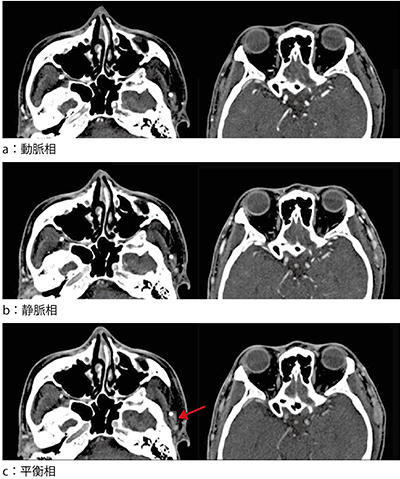

図2 造影ヘリカルCT

頬骨基部では石灰化巣と平衡相でわずかに造影される腫瘤(c←)が側頭筋内に存在し,側頭部では太い静脈と腫瘤が側頭筋表面に存在している。